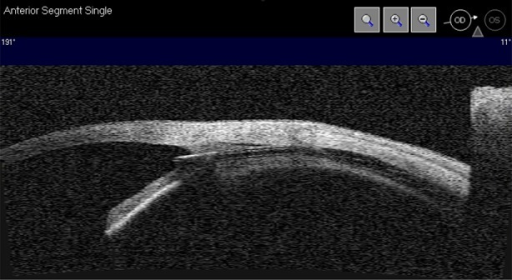

| Subconjunctival | 결막하 공간으로 배액 | XEN Gel Stent, Preserflo Microshunt |

| XEN | 결막하 배액 | Ab interno, bleb 형성 |

- XEN/Preserflo: Subconjunctival MIGS — bleb 형성 → trab에 가까운 효과